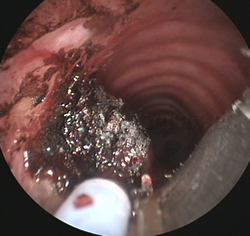

Fotorresección

con láser |